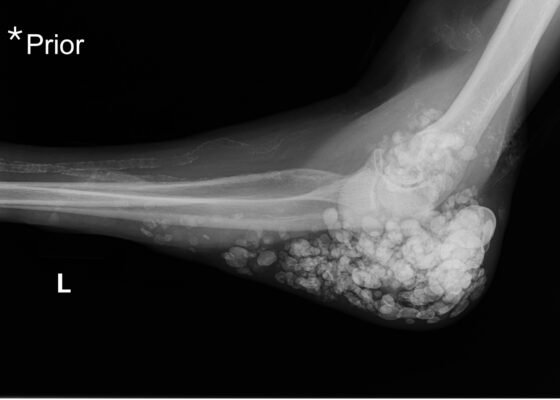

DOI: https://doi.org/10.21980/J87Q00X-ray imaging was obtained of the left elbow and showed soft tissue calcium deposits. Radiology stated, “massive periarticular calcinosis of renal failure obscures fine osseous detail. Several of the largest calcifications have decompressed since the prior exam and may contribute to the drainage observed clinically. Superimposed infection is not excluded.” X-rays with an asterisk are the comparison images from two months previous to the visit. Areas of decompression are highlighted in blue demonstrating that some of the larger calcified nodules are no longer present.